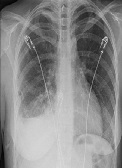

Combination of Unfractionated Heparin (UFH) and Triple Antiplatelet Therapy After Percutaneous Coronary Intervention (PCI) May Increase the Risk of Life Threatening Hemothorax in a Patient with Recent Rib Fracture

Javad Savoj, Asma Jamil, Syed Iftikhar, Rajesh Gulati*